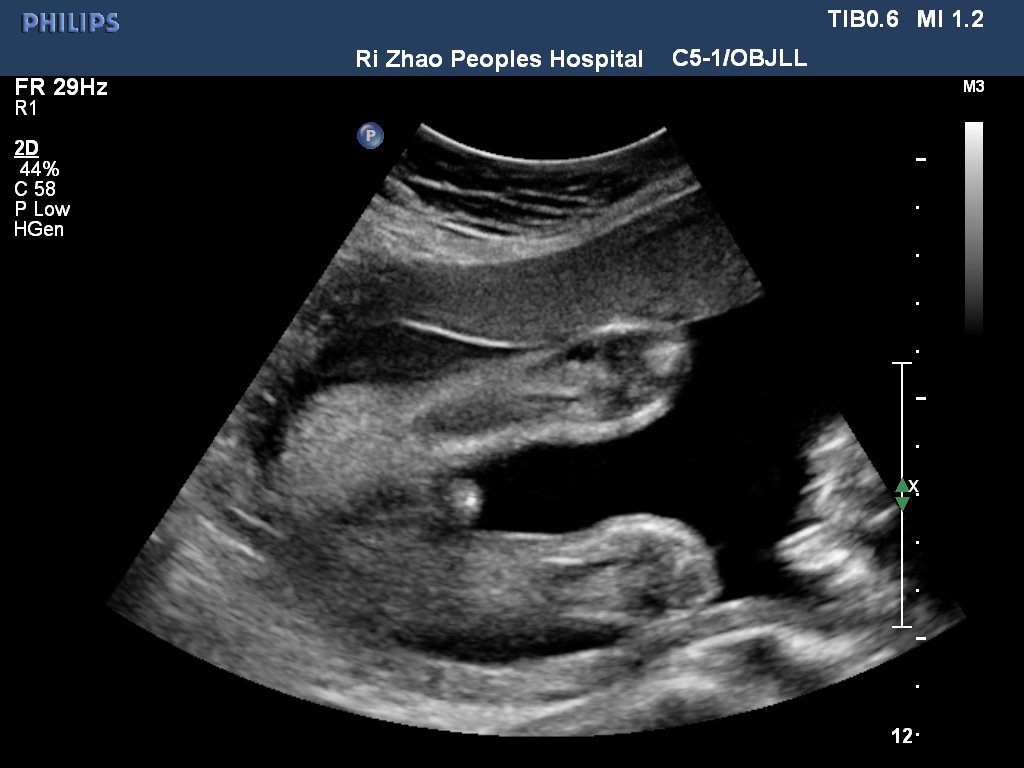

26+1的B超图像,有知道这个是胎儿的哪个部位么 点击展开 匿名用户 2013-07-22 10:24 满意回答 恭喜你了!男孩的几率很大! 符骊霞_HAgJ 2013-07-22 10:54 宝宝知道提示您:回答为网友贡献,仅供参考。 为您推荐: 其他回答 好像是个男孩子。 撒曼珠_h3Ea 2013-07-22 10:43 相关问题 关于B超图像,胎儿这个B超图片是哪个部位? 怀孕24周B超图像是宝宝的哪个部位?可以看出男女吗?纯属好奇,男宝女宝都喜欢… 15周b超可以看出胎儿性别了么?